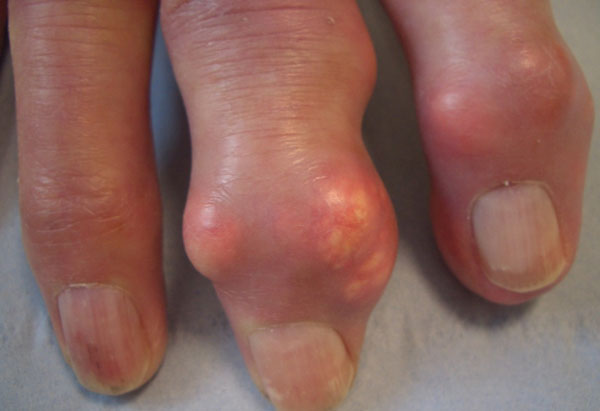

A less common presentation is insidious onset of chronic usage related joint pain, especially in joints already affected by osteoarthritis (e.g. finger interphalangeal joints with nodal osteoarthritis). Subcutaneous tophi can also be the presentation, especially in older people, see figure 3.

Tophi particularly target extensor surfaces of toes, fingers, heels, knees and elbows, appearing as nodules with heterogeneous consistency, sometimes with white-yellow discoloration (urate deposits are white).